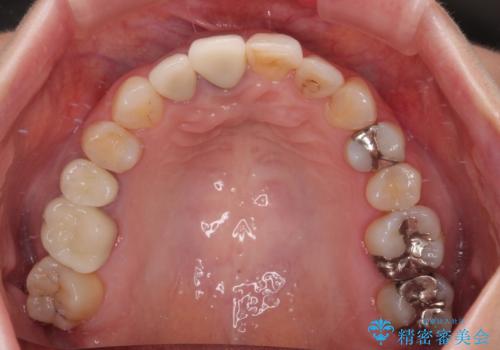

- 前歯のセラミッククランが外れてしまったとのことで来院された患者様です。

診察をしたところ、歯根に縦破折が認められ、抜歯が必要と判断されました。

抜歯、インプラント埋入、仮歯の装着が同時に可能な1DAYインプラントが適用可能と判断されたため、インプラントによる補綴治療を行うこととしました。